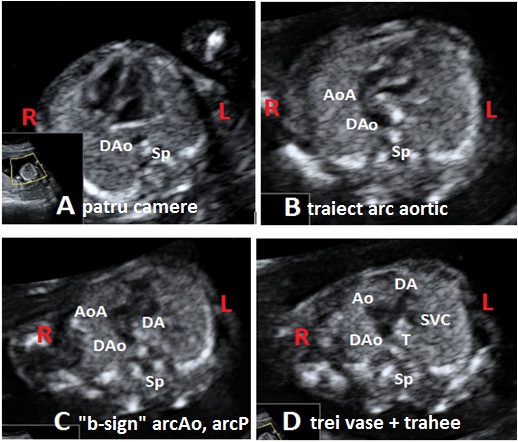

Anomaly: Arc aortic drept + Arc ductal la dreapta (Right aortic arch + patent right ductus) date: 2011-05-15

Aorta descendenta situata intratoracic la dreapta, arc aortic si duct arterial orientate la traheei. Morfologie normala a cordului, aspecte normale Doppler Color (imagini atasate).

Ecocardiografia trim. 2 confirma diagnosticul.